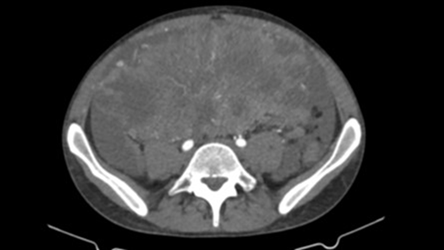

Following an ultrasound examination which revealed hypoechoic heterogeneous

masses, a contrast-enhanced computed tomography (ct) scan yielded mild ascites

and significant opacity of the peritoneal fat, along with heterogenous focal

lesions. The largest mass was located in the lesser pelvis, measuring 20 x 14.5

x 16 cm, accompanied by concurrent enhancement in the paracolic gutters and

omentum, indicating further peritoneal dissemination (figure 1a and 1b).

Figure 1a

& 1b: preoperative

contrast enhanced ct scan of the largest lesion measuring 20 x 14.5 x 16 cm.